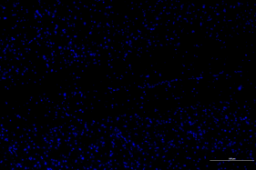

免疫熒光

正常對(duì)照組 模型組

脊髓損傷模型GFAP表達(dá)差異對(duì)比

免疫熒光技術(shù)是將免疫學(xué)方法(抗原抗體特異結(jié)合)與熒光標(biāo)記技術(shù)結(jié)合起來研究特異蛋白抗原在細(xì)胞內(nèi)分布的方法。由于熒光素所發(fā)的熒光可在熒光顯微鏡下檢出,從而可對(duì)抗原進(jìn)行細(xì)胞定位,并且可以通過熒光強(qiáng)度對(duì)檢測蛋白的表達(dá)量進(jìn)行半定量分析。